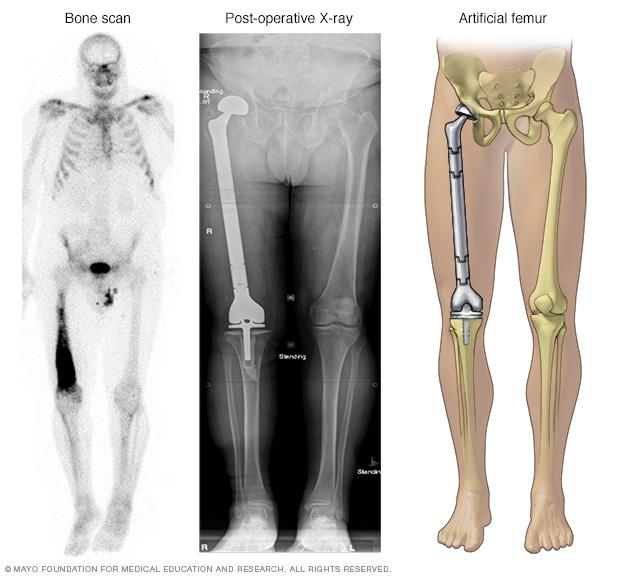

A bone scan (left) shows cancer in right thighbone, also called the femur. The entire thighbone, plus the hip joint and knee joint, were replaced with artificial components.

Chondrosarcoma treatment often involves surgery to remove the cancer. Other treatments might be recommended in certain situations. Which options are best for you depends on where your cancer is located, how quickly it's growing, whether it has grown to involve other structures, your overall health and your preferences.

• Cutting away the cancer and some healthy tissue around it. Most chondrosarcomas require a procedure to cut away more of the bone in order to remove all of the cancer. For chondrosarcoma in an arm or a leg, it might be necessary to remove the entire limb. When possible, surgeons remove the cancer in a way that preserves the limb. For example, the surgeon might remove the affected bone and replace it or reconstruct it (limb salvage surgery).